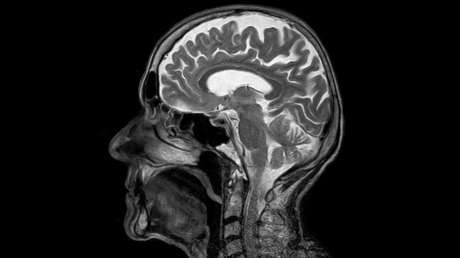

Un equipo de científicos del Instituto de Investigación del Cáncer de Londres, Reino Unido, ha realizado el estudio sobre el cáncer cerebral más exhaustivo de la historia y ha identificado 13 alteraciones genéticas previamente no descubiertas que aumentan el riesgo de desarrollar glioma, la forma más común de esta enfermedad.

Los gliomas constituyen alrededor de un 40% de los tumores cerebrales diagnosticados, y hasta la fecha no existe un procedimiento fiable para detectarlos de antemano. Los métodos existentes para tratar los gliomas tampoco son muy eficaces, como señala el equipo en su informe sobre el estudio.